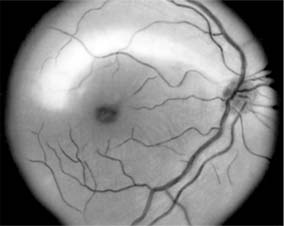

Figure 14-11

Figure 14-11: Retinal nerve fiber layer in demyelinating optic neuropathy of multiple sclerosis. The upper temporal nerve fiber bundles show multiple slit-like areas of thinning (arrows) representing retrograde axonal atrophy from subclinical disease in the optic nerve. Vision in the eye was 20/20.